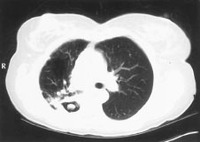

Sinal do "crescente aéreo" em aspergilose pulmonar avançada

Do acervo do Dr. P. Chandrasekar; usado com permissão